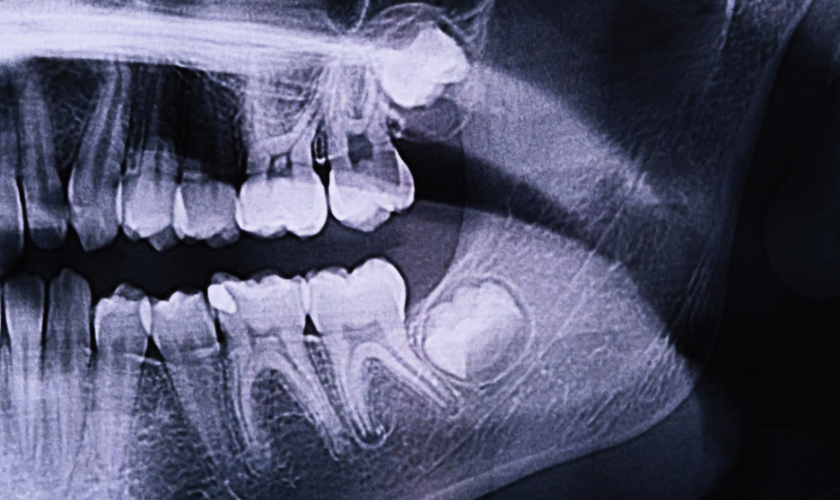

- X-rays: Dental X-rays, including panoramic X-rays, will reveal the position and angulation of the wisdom teeth, helping determine if they are impacted and their proximity to nerves and other structures.